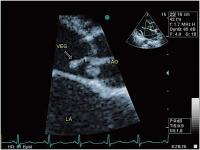

Abbildung 1: Endokarditische Vegetation (Veg) an der akoronaren Taschenklappe (Ao = Aorta ascendens; LA = linker Vorhof)